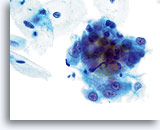

ThinPrep® Pap Test

Adenokarzinom

ThinPrep® Pap Test

Adenokarzinom